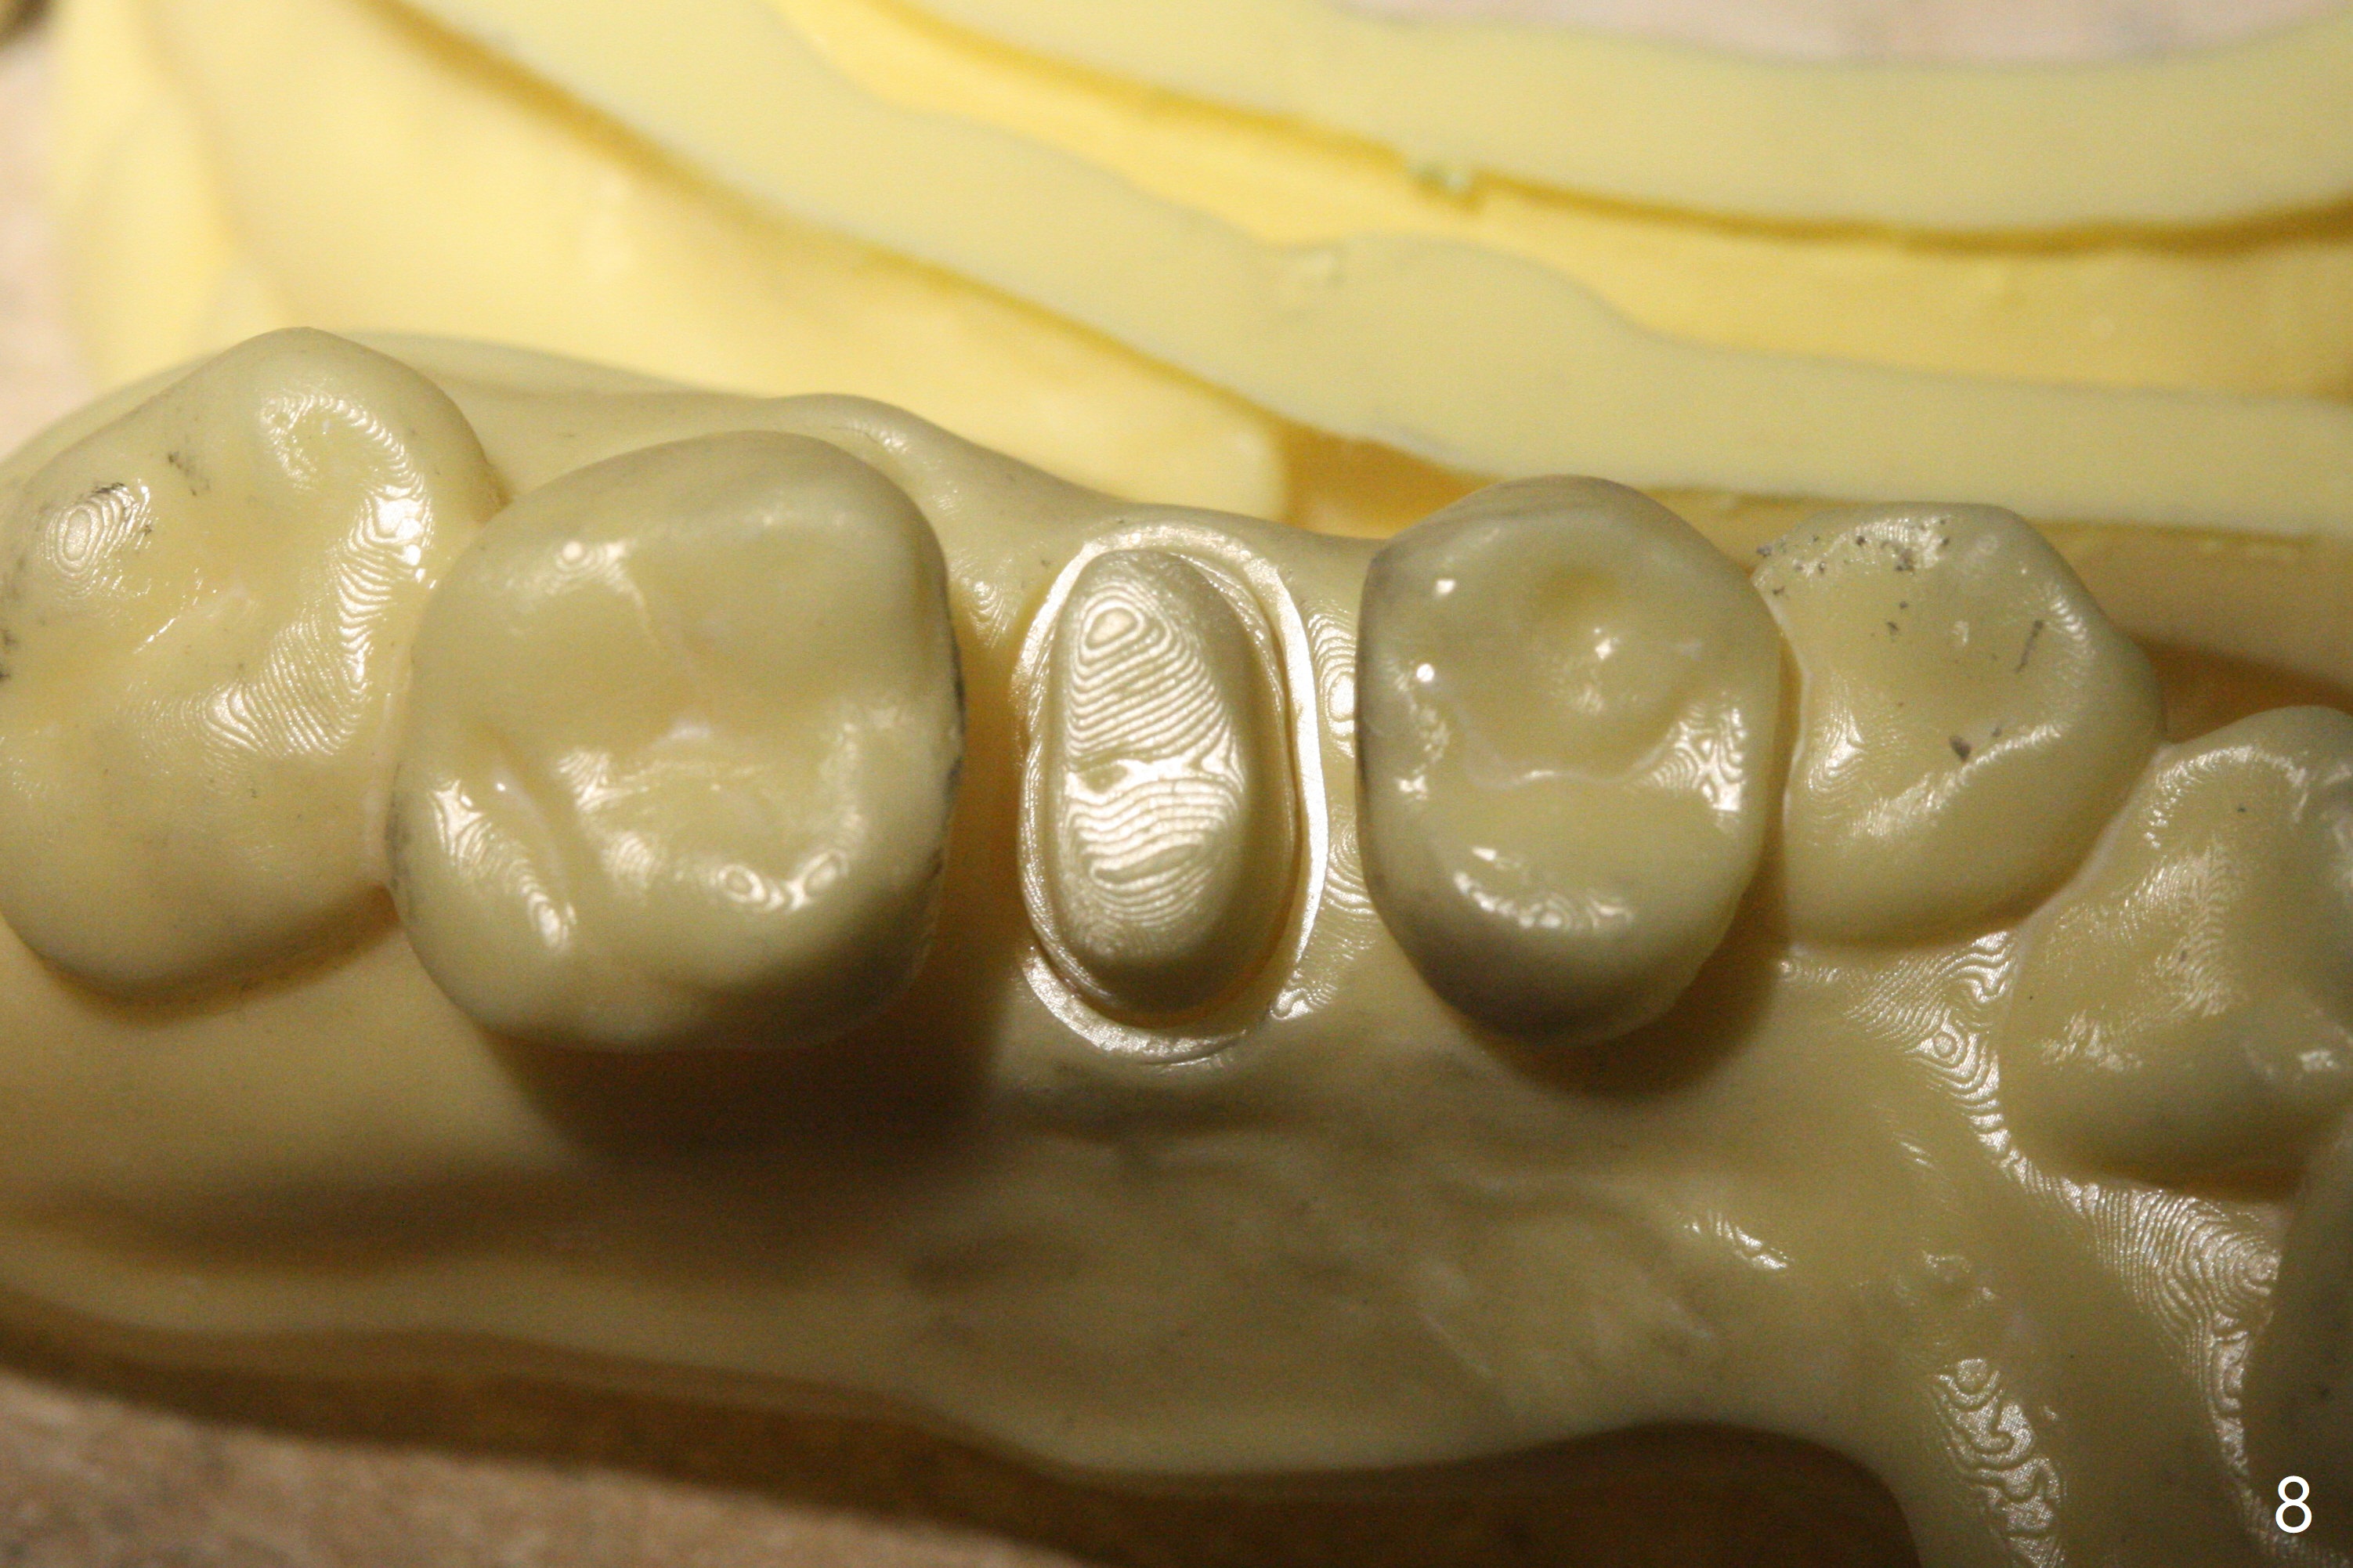

52岁女去年在外州开始4号牙根管治疗(图一),由于新冠病毒和搬家而拖延治疗,现在要求完成根管治疗(图二,三),B: 颊侧(主牙胶尖:20/.04);L: 舌侧(旋转锉:20/.04)。Shining口扫(图四(咬合面观),五(舌侧观),六(颊侧观;对合:局部托牙 (RPD)))。为了保险起见,要求实验室制作两个牙冠:取模,口扫。帮助实验室建立完善数字化系统,从而帮助临床工作。备牙边缘清晰(图八)。牙冠边缘与数字模型(图九)和牙齿吻合,天衣无缝。

Shining Oral Scanner and Crown Prep Margin

Root canal therapy (RCT) was initiated for the tooth #4 of a 52-year-old lady out of state approximately 8 months earlier (Fig.1). The patient requested finishing the treatment and permanent crown fabrication. The buccal (Fig.2 B (master cone 20/.04)) and lingual (L (rotary file 20/.04))) canals fuse near the apex. RCT was done with insertion of 20/.04 and 20/.06 master cones in the buccal and lingual canals, respectively, followed by composite build-up (Fig.3). With basically shoulder margin (not feather margin, chamfer margin ok), it is easy to scan (Fig.4-6 (RPD: removable partial denture)). Return to Oral Scanner Xin Wei, DDS, PhD, MS 1st edition 06/05/2021, last revision 06/25/2021